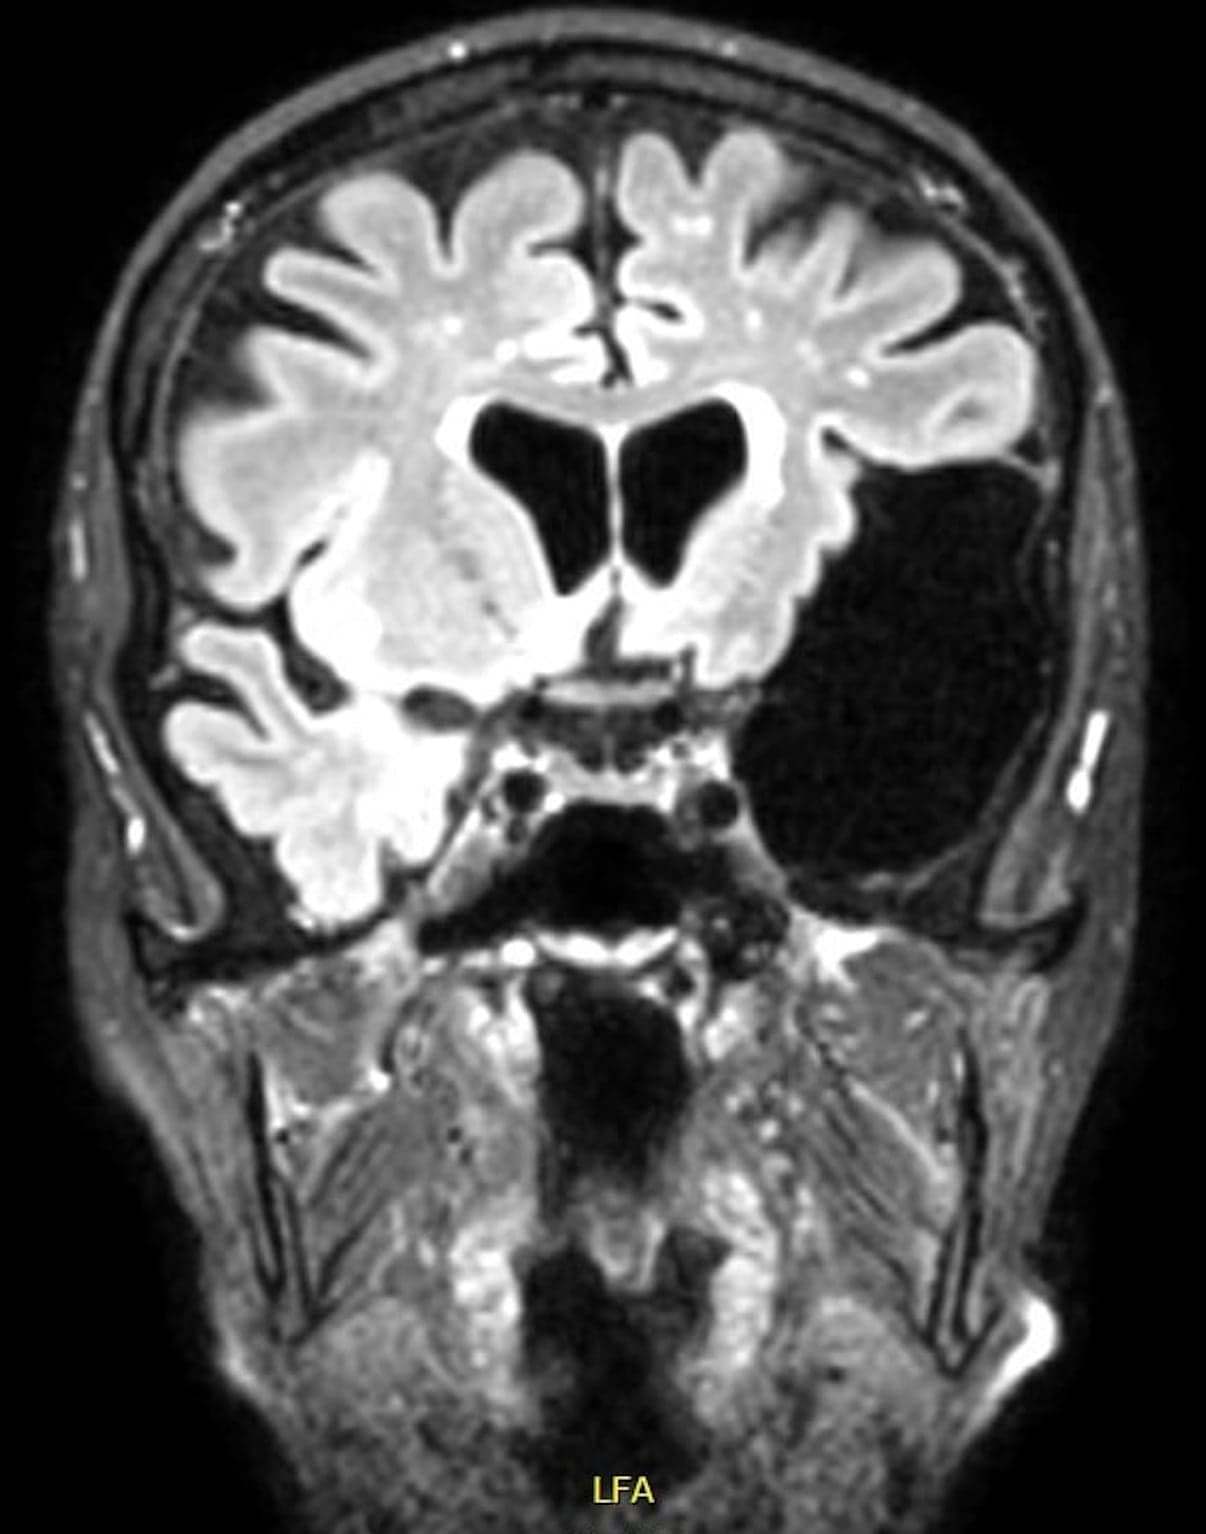

Arachnoideacyster (Figur 1 og Figur 2) er hyppige tilfældige fund på hjerneskanninger med en prævalens på 2% i befolkningen [1]. De betragtes som kongenitte strukturer, som udgår fra arachnoidea mater, den midterste hjernehinde, og indeholder cerebrospinalvæske. De kan opstå overalt, hvor der findes arachnoidea, inklusive i spinalkanalen. De intrakranielle arachnoideacyster ses oftest i fossa cranii media (55%), hvor de typisk er placeret mellem cerebrum og kraniet [1]. De findes her lidt hyppigere i venstre end i højre hemisfære, og blandt patienterne ses en lille overvægt af mænd [2].

MR-skanningsbillede af stor arachnoideacyste i venstre temporal­region.